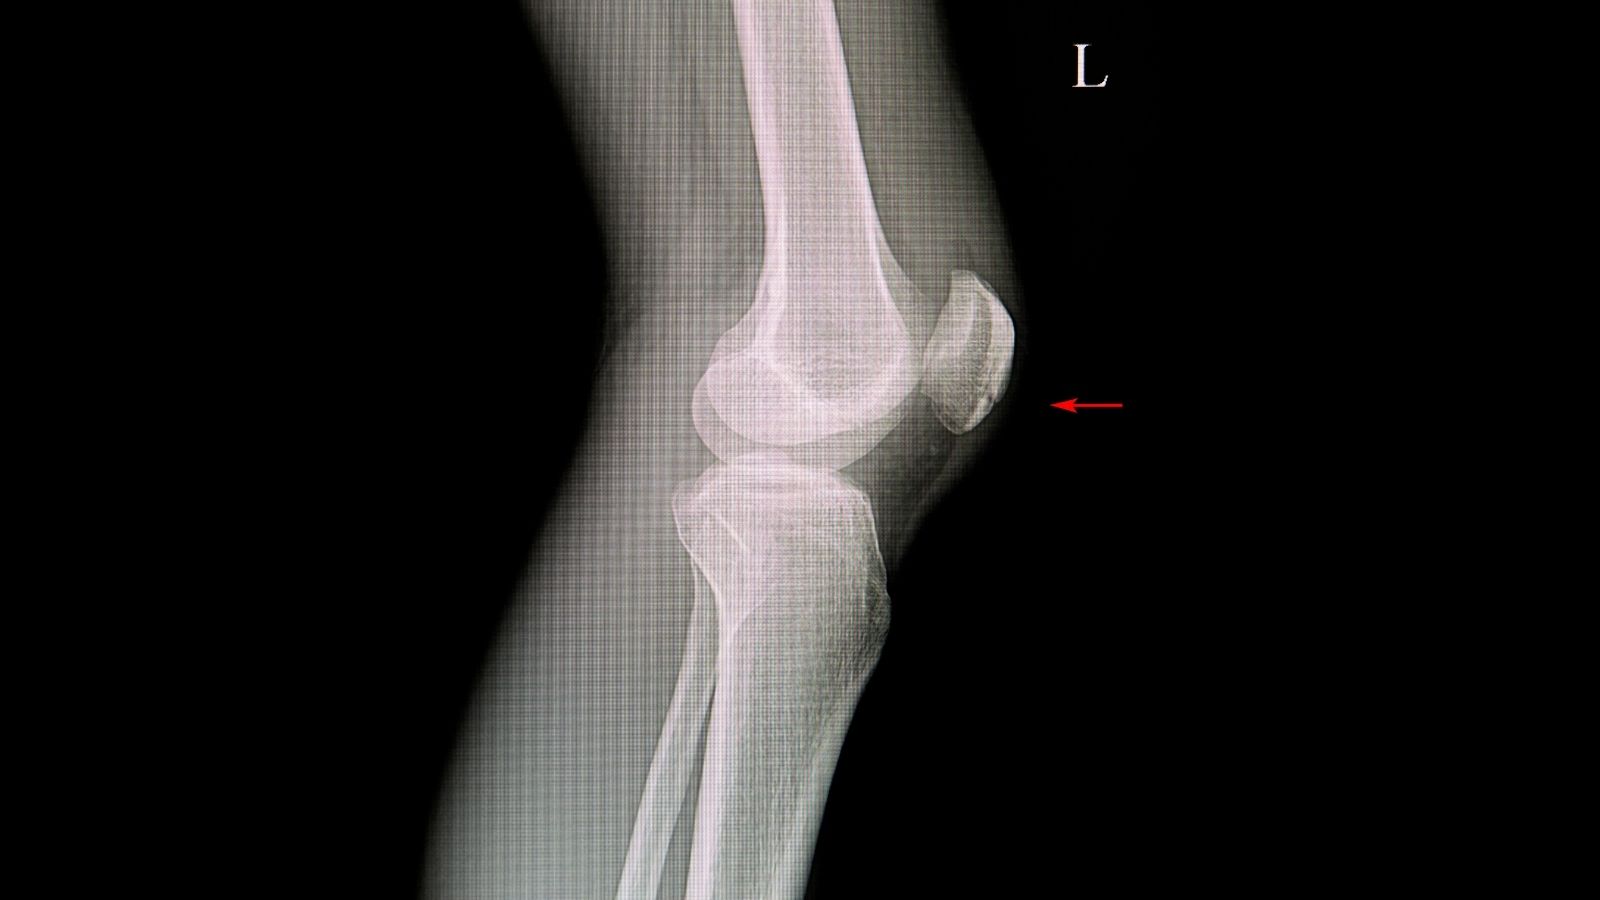

Diz artroplasti revizyonu tanı yöntemleri, ağırlıklı olarak radyografi ve BT analizleriyle protezin pozisyonunu, kemik kaybını ve olası enfeksiyon bulgularını değerlendirmeye dayanır. Laboratuvar testleri, enfeksiyon ayırıcı tanısını destekler.

| Planlama Süreci | Klinik değerlendirme, röntgen ve ileri görüntüleme (BT/MRG), enfeksiyon taramaları (kan testleri, eklem sıvısı analizi), protez bileşenlerinin yapısal durumu analiz edilir. |

| Takip ve Kontrol | Klinik muayene, röntgen ile protez stabilitesi değerlendirilir. Enfeksiyon veya mekanik komplikasyon belirtileri açısından düzenli izlem gerekir. |

Başarılı bir revizyon cerrahisinin sırrı, ameliyathaneye girmeden önce yapılan detaylı planlamada gizlidir. Dizinizi açtığımızda neyle karşılaşacağımızı önceden bilmek zorundayız. Bunun için röntgenlerin yanı sıra bilgisayarlı tomografi (BT) gibi ileri görüntüleme yöntemlerini kullanırız. Burada iki ana şeyi değerlendiririz: Kemik kaybının miktarı ve bağların durumu.

Kemik kaybı bizim için en büyük teknik zorluktur. Eski protez gevşediğinde, hareket ettikçe etrafındaki kemiği “törpüler” ve eritir. Biz bu kemik kayıplarını “AORI” dediğimiz bir sistemle sınıflandırırız. Eğer kemik kaybı azsa işimiz nispeten kolaydır. Ancak büyük boşluklar varsa, yeni protezin havada asılı kalmaması için bu boşlukları nasıl dolduracağımızı önceden hesaplamalıyız.